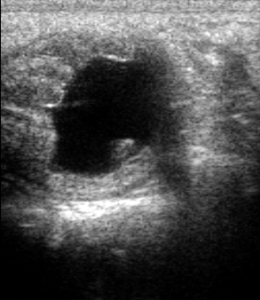

W przypadku obumarcia zarodka (Early Embryonic Death) i utrzymującego się CL możliwe stężenia progesteronu wskazujące na ciążę. Wyniki badania powinno rozpatrywać się w powiązaniu z obrazem USG.

Cel: ocena fazy cyklu płciowego oraz aktywności jajników. Wzrost obserwowany u klaczy ciężarnych powyżej 60. dnia ciąży. Silny wzrost stężenia może również wskazywać na przetrwały nieowulujący pęcherzyk jajnikowy. W przebiegu “cichej rui” stężenie estradiolu może być niższe niż w przypadku rui prawidłowej.

Interpretacja:

< 10 pg/ml – małe pęcherzyki, co odpowiada fazie diestrus/wczesnej folikularnej/anestrus sezonowemu

11 – 15 pg/ml – średnie pęcherzyki (średnica pomiędzy ≈ 20 – 30 mm), co odpowiada fazie folikularnej

> 15 pg/ml – duży pęcherzyk średnica ≥ ≈ 30 mm (pęcherzyk przedowulacyjny), co odpowiada estrus

> 30 pg/ml – podejrzenie ziarniszczaka lub przetrwałego pęcherzyka nieowulacyjnego

Zalety: rutynowe badanie, możliwość potwierdzenia subklinicznej aktywności pęcherzyków jajnikowych.

Ograniczenia: wynik badania należy rozpatrywać łącznie z obrazowaniem ultrasonograficznym.